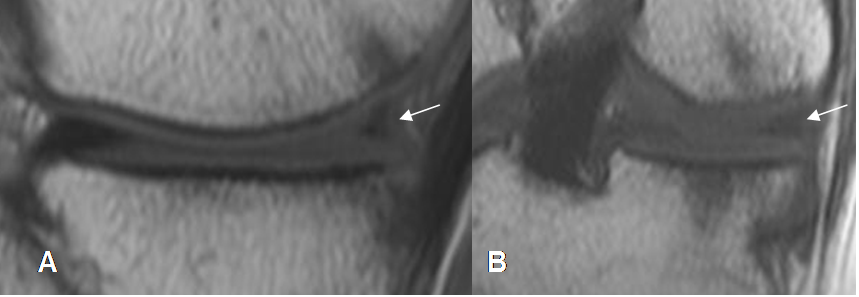

Fig 71. Ruptura meniscal horizontal.

A: RM sagital en T1 y B: RM sagital en STIR. Imagen en sentido horizontal que se comunica el borde libre y la superficie articular inferior, por ruptura meniscal.

Fig 72. Ruptura meniscal vertical.

A y B: RM sagital en STIR. Imagen en sentido vertical que se comunica con la superficie articular inferior, por ruptura meniscal.